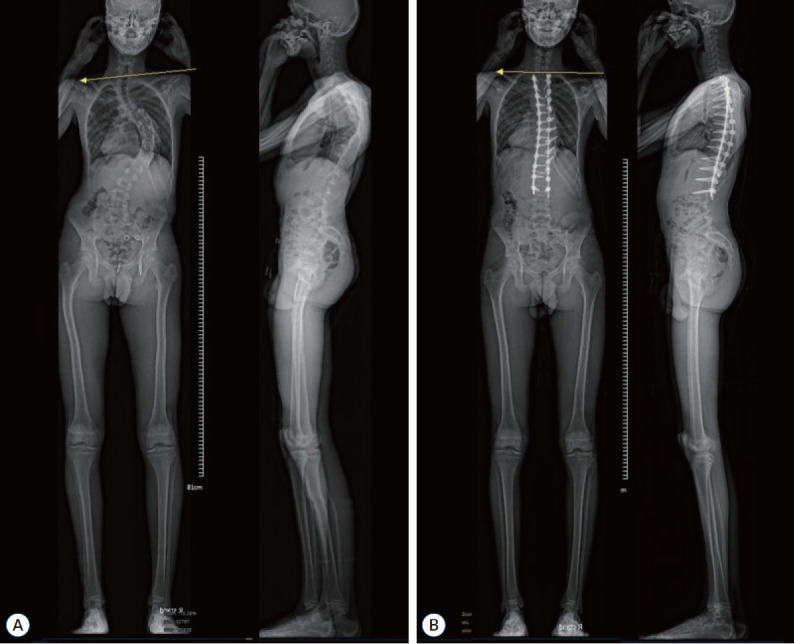

目的:本研究旨在评价由单一神经外科医生手术的青少年特发性脊柱侧凸(AIS)患者的临床和影像学结果。方法:在2011年1月至2024年1月期间,共调查了139例连续接受单一神经外科医生矫正手术的AIS患者。椎弓根螺钉节段内固定用于畸形矫正。评估人口统计学信息、采用Lenke分类的曲线结构类型、矫正程度、融合水平总数、并发症和临床/影像学结果。结果:大多数患者为青春期女孩(105 vs 34),平均年龄分别为15.9 vs 16.0。平均随访时间为4.5年(0.1 ~ 13.0年)。9例(6.6%)为左旋侧凸,其余130例为右旋侧凸。4例(2.8%)患者偶然诊断为伴脊髓空洞的Chiari畸形。在有Chiari畸形的患者中,2例(50%)有左旋侧凸。平均融合节数为11.2个。Cobb角在主结构曲率处的平均值为63.4°(43°-125°)。主要结构曲线的平均修正百分比为78.8%。术后最终SRS-22平均评分为4.3±0.4分,明显高于术前的3.8±0.5分(P < 0.001)。手术后,没有观察到神经功能缺损或需要重新定位螺钉的病例。一例患者接受翻修融合伸展手术治疗术后肩部不平衡。结论:经神经外科医生治疗的AIS患者具有可接受的临床和影像学结果。然而,AIS手术需要对小儿脊柱畸形有一个基本的了解,这是至关重要的。此外,脊柱外科医生在治疗左侧凸患者时应谨慎。

Results: Most patients were adolescent girls (105 vs. 34) with an average age of 15.9 vs. 16.0, respectively. The average duration of follow-up was 4.5 years (0.1-13.0). Nine patients (6.6%) had levoscoliosis, and the remaining 130 had dextroscoliosis. Chiari malformation with syringomyelia was incidentally diagnosed in four patients (2.8%). Of the patients having Chiari malformation, two (50%) had levoscoliosis. The mean number of fused levels was 11.2. The mean value of the Cobb angle of the major structural curvature was 63.4° (43°-125°). The major structural curve's average percentage of correction was 78.8%. The final postoperative SRS-22 average score significantly improved to 4.3±0.4 compared with the preoperative score of 3.8±0.5 (p<0.001). After the surgery, there were no observed cases of neurological deficits or need for screw repositioning. Revision fusion extension surgery was performed on one patient to treat postoperative shoulder imbalance.